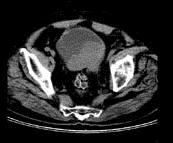

问题 男,56岁,无痛性肉眼血尿2个月,CT检查如图所示,应诊断为 ( )

选项 A、膀胱平滑肌瘤 B、膀胱息肉 C、膀胱血块 D、膀胱癌 E、膀胱结石

答案 D